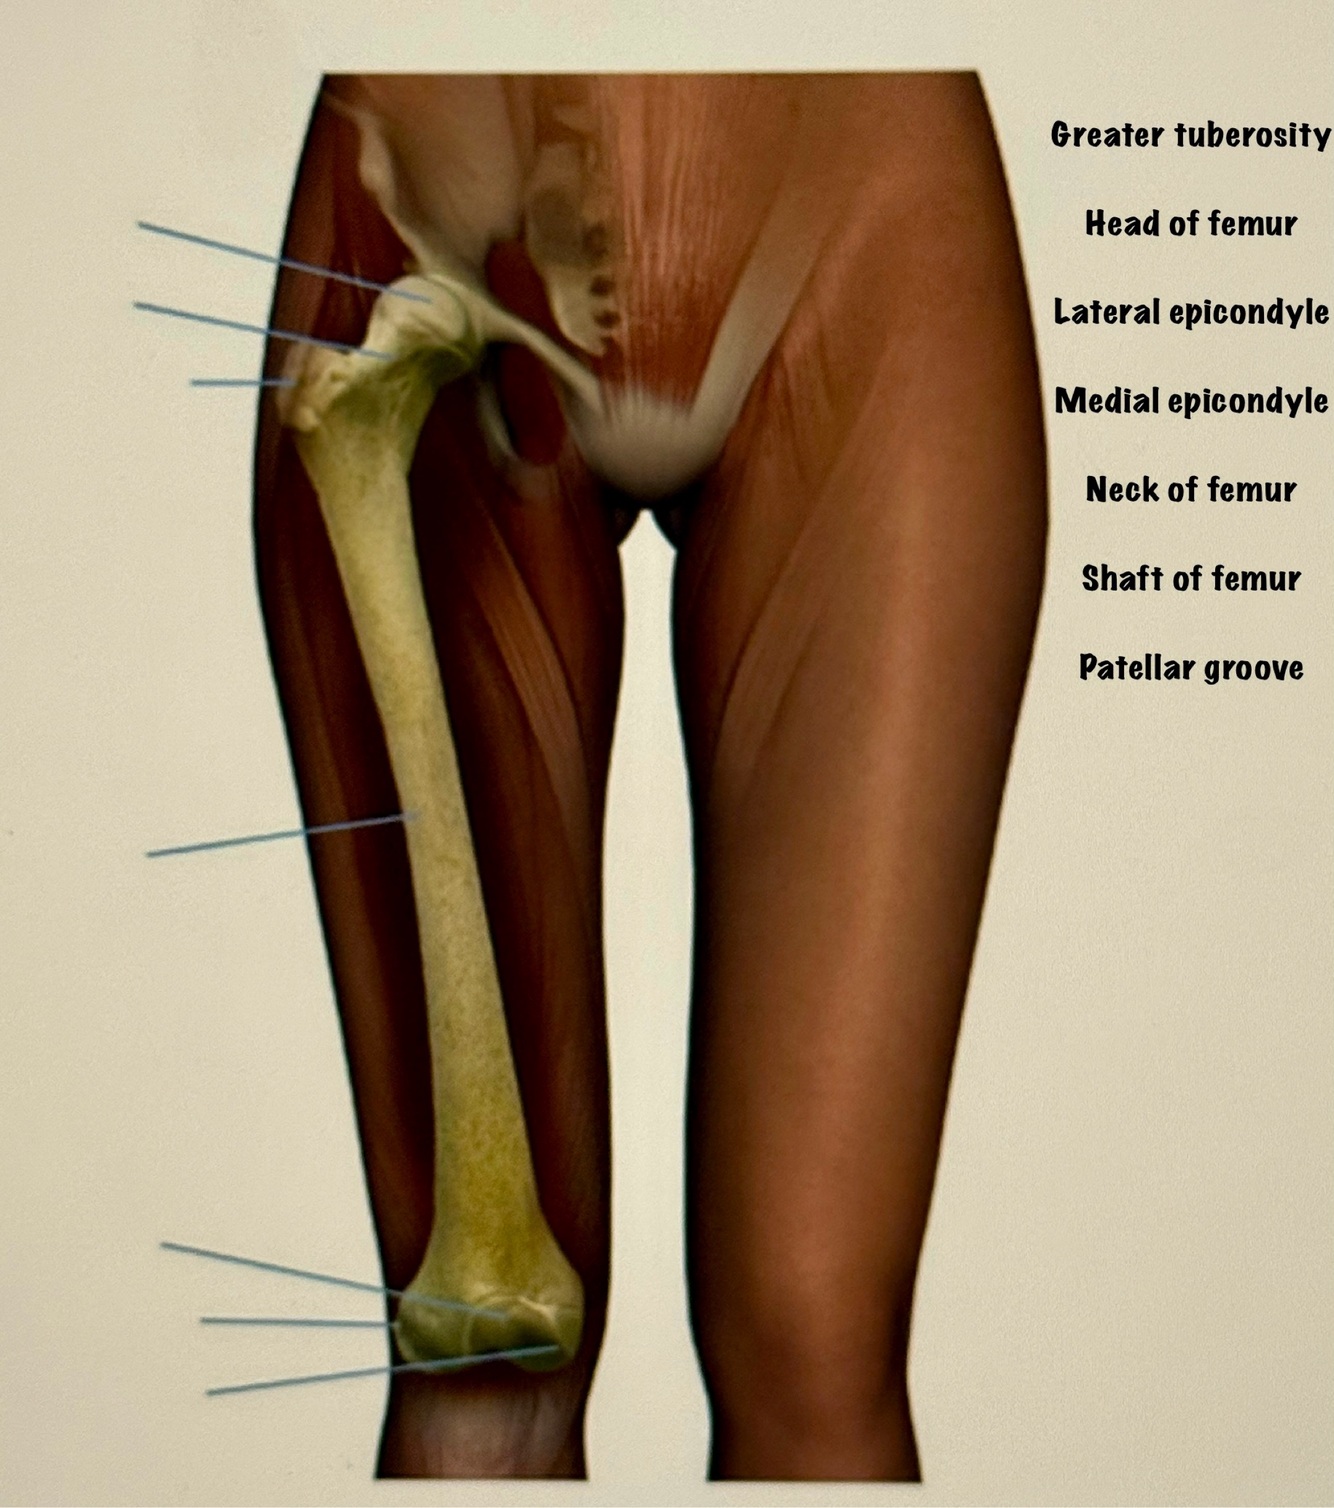

Letter D points to

Acetabulum

Letter E points to the

Ischium

Letter G points to the

Superior pubic ramus